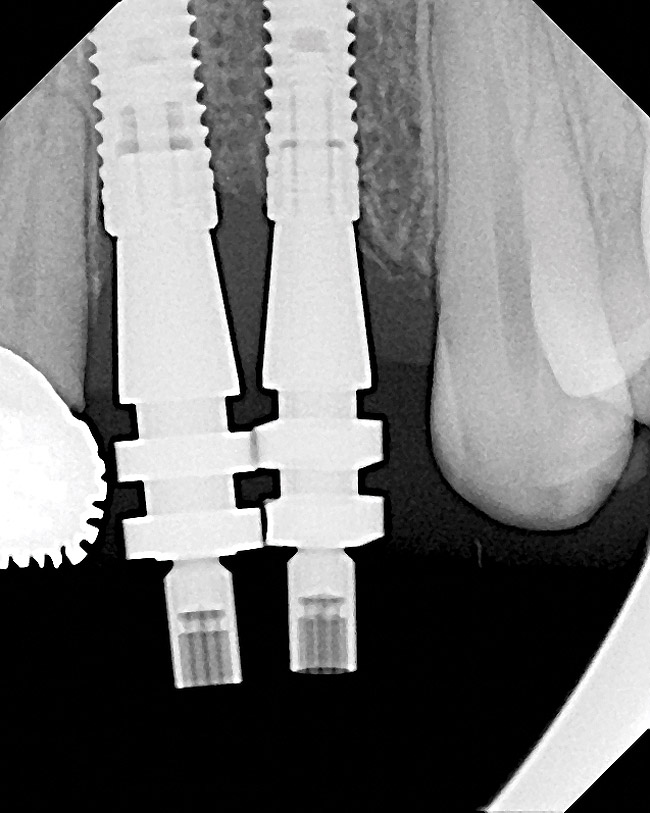

Figure 30  (Case 3) Laboratory view showing compromised depth of implants due to a lack of crestal height.

Figure 30